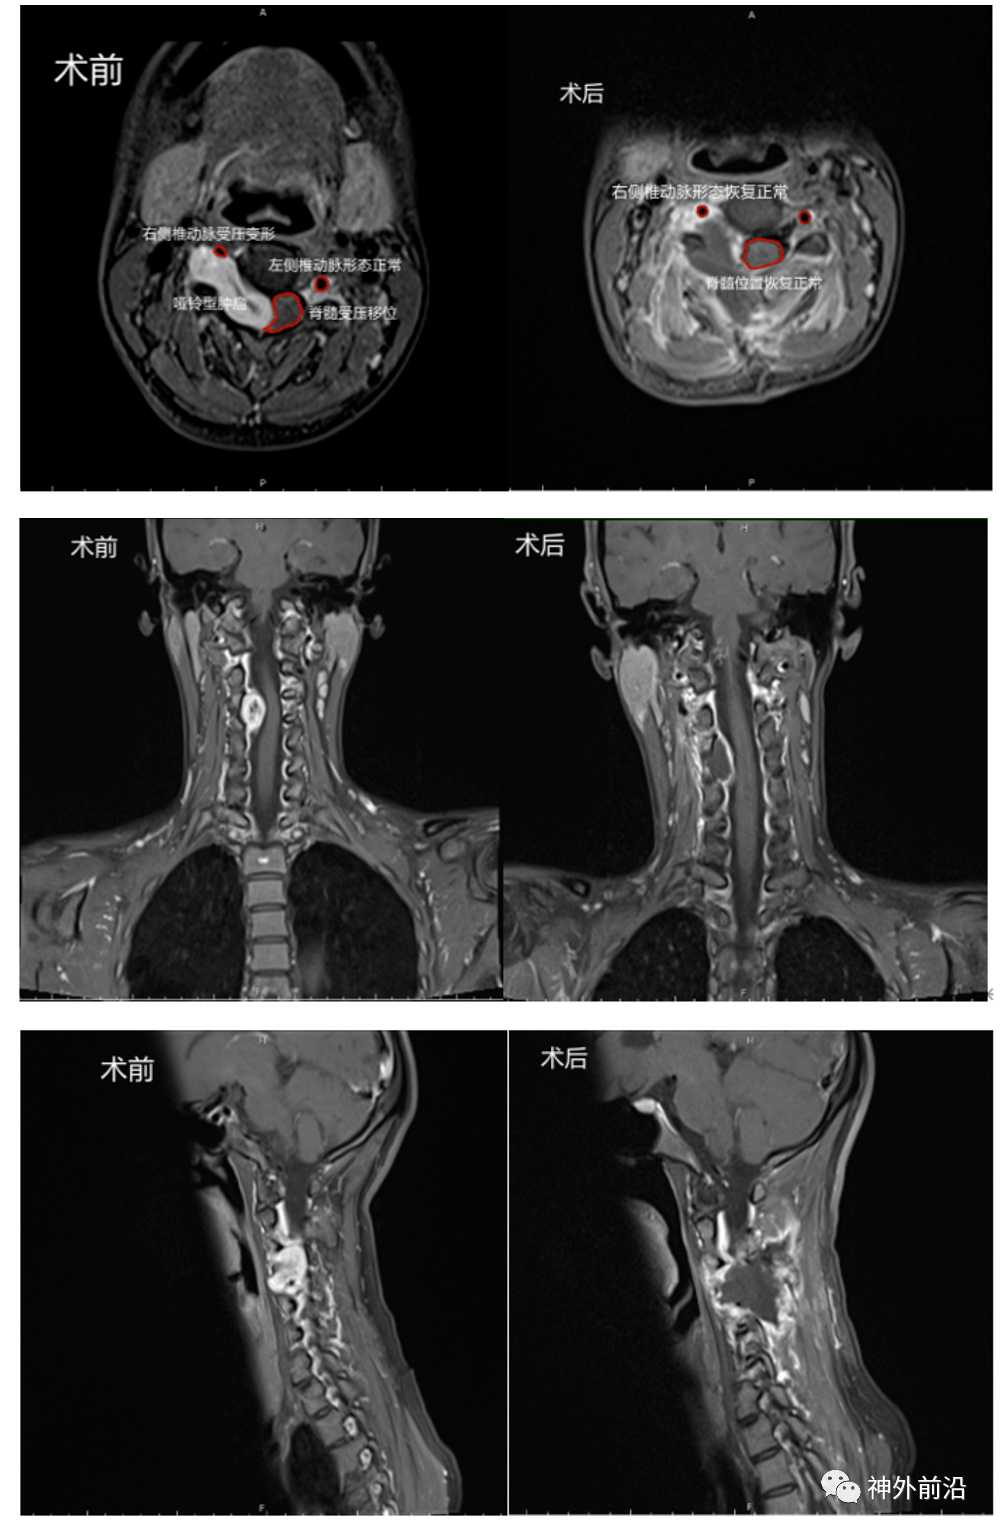

颈椎哑铃形肿瘤 女性50岁,双手麻木伴右侧上下肢无力2年 - 好大夫在线